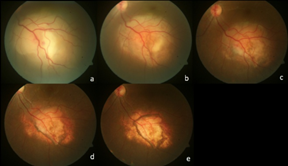

An 18-year-old female, presented with sudden diminution of vision since 7 days in left eye. The best corrected visual acuity in right eye was 20/20 and left eye was 20/100 on Snellen’s chart. On examination anterior chamber and vitreous was quiet, disc was within normal limits with a yellowish white subretinal mass with small hemorrhage on the surface along the inferior arcade up to mid periphery measuring 12DD(disc diameter) (Figure 1) with presence of SRF involving the macula and the inferior quadrant was noted. The b-scan showed mild vitreous echoes with a dome-shaped choroidal lesion with a dimension of 6.82x14.50mm, with no surface reflectivity irregular low-to-medium internal reflectivity with the presence of an anechoic space in the mass, suggestive of an inflammatory etiology (Figure 2). Complete physical examination and medical evaluation findings, including a chest x-ray film, were normal. Results of a blood uveitis workup (serum angiotensin converting enzyme, serum lysozyme, Venereal Disease Research Laboratory titer, Toxoplasma titer, Toxocara titer) were negative. A purified protein derivative skin test was highly positive (induration, 20X20 mm). Optical coherence tomography showed subretinal fluid (SRF) at macula (Figure 3). We made the clinical diagnosis of solitary choroidal tuberculoma in an immunocompetent patient in whom routine investigations failed to identify systemic tuberculosis infection. The patient was started on isoniazid, rifampin, and ethambutol for a 6-month period. Under supervision of a physician, systemic steroids (1 mg/kg/day) in tapering doses were given. The choroidal granuloma subsequently decreased in size (Figure 1A‒C) (Figure 2B) over the following 3 months to form a flat chorioretinal scar. After 3 months of oral ATT and steroids, no improvement in visual acuity (20/100) was noted due to persistent SRF at macula (Figure 3B), intravitreal triamcinolone acetonide 2 milligram was planned and resulted in complete resolution of the SRF at macula (Figure 3C) with shrinkage of the choroidal lesion at 4 month (Figure 1D,E).The final visual acuity was 20/20 and was maintained till 1 year follow up.

Figure 1 (A) Shows yellowish white subretinal mass along the inferior arcade up to mid periphery. (B) At 1 month post starting oral ATT and steroids shows reduction in the size of granuloma. (C) At 3rd month shows further reduction in the size of granuloma with the inferior margin shows signs of atrophy and pigmentary changes. (D) 1 week post intravitreal triamcinolone acetonide shows gross atrophy at the margins with marked shrinkage in the center. (E) Shows complete shrinkage of the granuloma with central scarring (6th month).